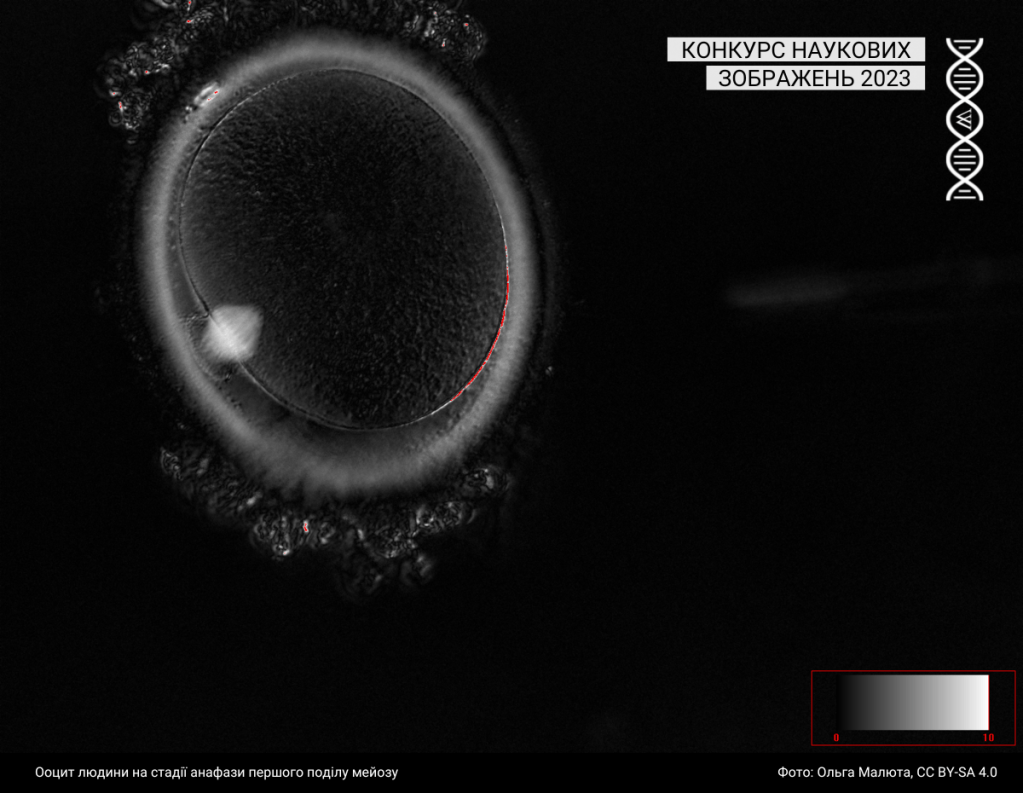

Під цю категорію підпадають світлини, зроблені за допомогою різних методик мікроскопії. Минулого року до цієї категорії учасники та учасниці завантажили 43 фотографії.

Спеціальна відзнака журі

Журі призначили спеціальну відзнаку серії зображень однієї авторки: https://w.wiki/99qJ, https://w.wiki/99qK, https://w.wiki/99qL, https://w.wiki/99qM